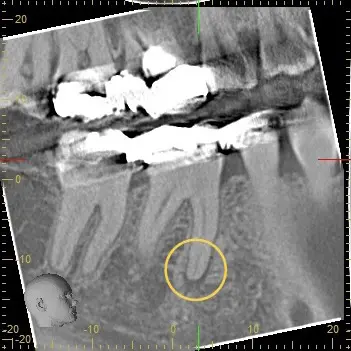

(画像は、「他の歯科医院で銀歯の詰め物をした歯が痛い」と来院された患者さんで、根尖病変を発見したCT画像。感染根管治療が必要な状態。【提供:松川デンタルオフィス】)

歯の根の中(根管内部)は非常に複雑な構造をしており、患者さん一人ひとり形が異なります。

そこで、実際に治療を始める前に欠かせないのが、歯や顎などのお口周りを三次元(3D)で立体的に撮影できる「歯科用CT」による精密検査です。

歯科用CTはレントゲン写真では見落としてしまうような部分(歯や根管が重なり合っているような部分)も多角的に撮影することが可能なので、隠れた根管や歯の根の先の膿(病巣)を見つけ出すのに役立ちます。

これにより、「患部を綺麗に取り除いたはずなのに痛みが再発して再治療」というリスクを防ぐことにつながります。